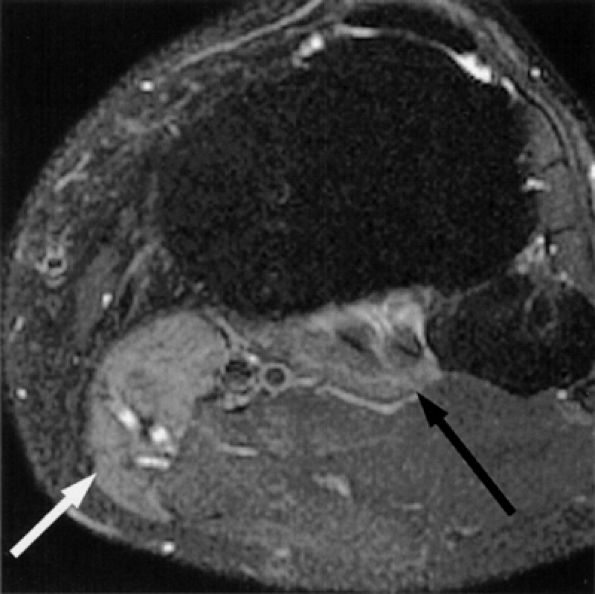

FIGURE 6.30 ● Common peroneal neuropathy with denervation atrophy and edema secondary to varicosities. (A) Axial T1-weighted image demonstrates denervation atrophy of the anterolateral muscles, predominantly the anterior tibial muscle (arrow). (B) Axial T2-weighted image depicts varicosities (arrowheads) next to the peroneal nerves and denervation edema of the anterior tibial muscle (arrow).

FIGURE 6.31 ● Surgically proven common peroneal neuropathy and denervation secondary to a hypertrophied biceps femoris muscle. (A) Axial T1-weighted image showing the common peroneal nerve (arrow) entrapped between a hypertrophied short head of the biceps femoris muscle (white asterisk) and the lateral head of the gastrocnemius muscle (black asterisk). (B) Axial T2-weighted fat-suppressed image displaying denervation edema in the anterolateral compartment muscles (arrows).